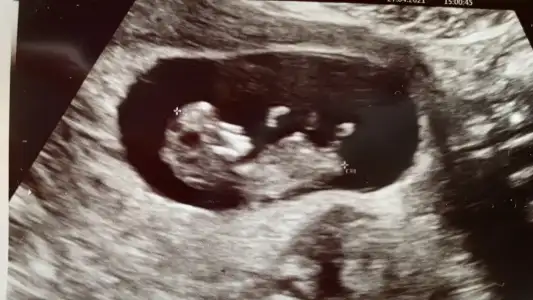

Ikra meyra Ikra meyra merhabalar ☺️ sanırım nub belli değil ama şansımı denemek istedim 11+2 yiz bugün tahmininiz nedir 🌺

çok merak ediyorum cinsiyetiiii 🙈❤️